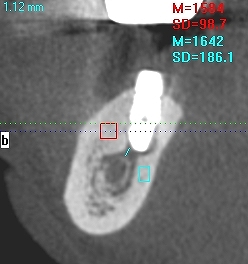

骨が硬いケースは海綿骨も少なく下顎管との距離を測るのが難しいケースになります。 | |広島市安佐南区の歯科医院 骨が硬いケースは海綿骨も少なく下顎管との距離を測るのが難しいケースになります。 トップ お知らせ・ブログ 骨が硬いケースは海綿骨も少なく下顎管との距離を測るのが難しいケースになります。 骨が硬いケースは海綿骨も少なく下顎管との距離を測るのが難しいケースになります。 Web診療予約 初めての方へ 選ばれ続ける理由 院内設備について 歯が痛いしみる一般歯科 歯がぐらぐらする歯周病 健康な歯を保ちたい予防歯科 子供の虫歯予防をしたい小児歯科 銀歯をセラミックに審美歯科 白い歯を目指しませんか?ホワイトニング 矯正専門医がいるので安心矯正歯科 抜けた歯を補いたいインプラント・入れ歯 医院案内 スタッフ紹介 メリィハウス歯科クリニックオフィシャルホームページ ラベンダー歯科クリニックオフィシャルホームページ お知らせ・ブログ ホーム 診療科目 一般歯科 歯周病治療 予防治療 小児歯科 審美治療 ホワイトニング 矯正歯科 入れ歯・インプラント マウスピース矯正 初めての方へ 院長・スタッフ 設備紹介 医院案内・アクセス メニューを閉じる